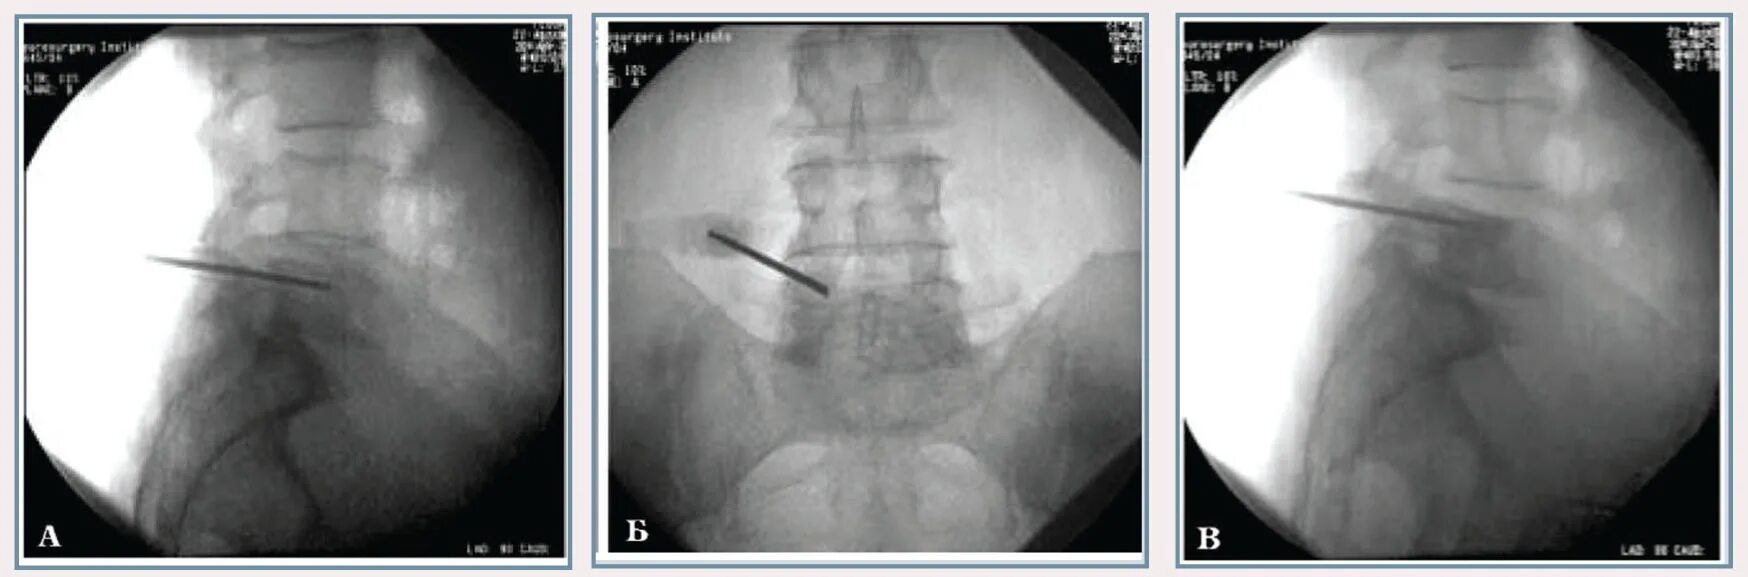

Метастазы щитовидной железы в легкие